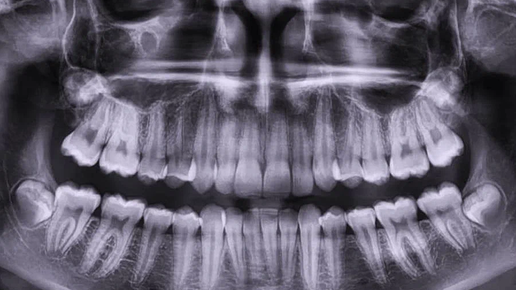

Как оценить успех лечения: фото-протокол и панорамный снимок

Одним из ключевых вопросов пациентов является: «Как лучше всего проверить, действительно ли лечение прошло хорошо?» Сегодня есть два мощных инструмента — фото-протокол и панорамный снимок (ОПТГ / ортопантомограмма). Давайте разберёмся, зачем они нужны, как используются, и как это делает ОМЦИП особенно качественно. Фото-протокол — это серия фотографий полости рта, сделанных до, во время и после лечения. Такие фотографии фиксируют состояние зубов, десен, прилегающих тканей, а также динамику изменений...